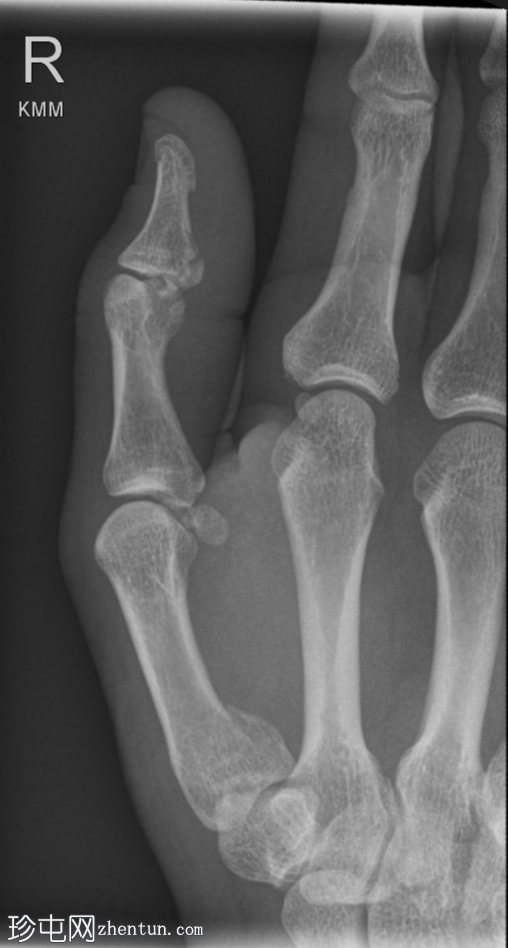

正位

右拇指远节指骨掌侧关节内轻度移位骨折,可能为撕脱性骨折。关节内可见轻微皮质台阶。

第一掌骨基底部可见轻微移位骨折,根据骨折轨迹推测可能为关节内骨折,但关节内皮质台阶不明显。若临床治疗方案改变,可能需要进一步

影像

学检查。第一腕掌关节解剖对位良好。